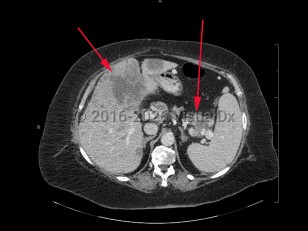

Metastatic pancreatic carcinomaMetastatic pancreatic carcinoma

Aortic dissectionAortic dissection

Abdominal aortic aneurysmAbdominal aortic aneurysm